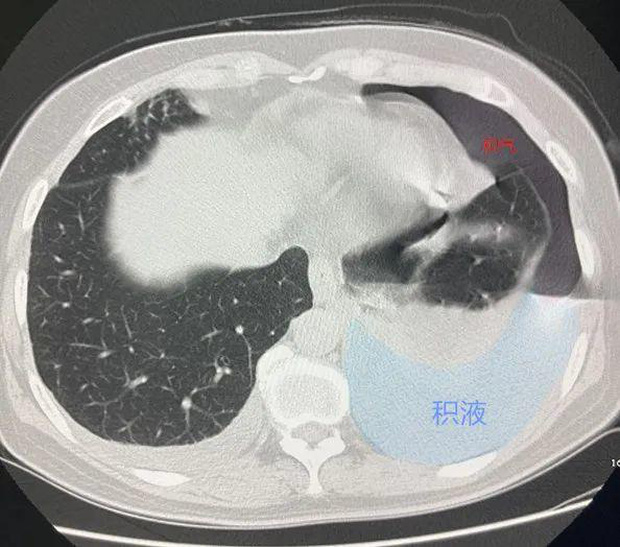

Lần này đến bệnh viện, cô được chụp CT, các bác sĩ phát hiện lồng ngực của cô có nhiều khí và chất lỏng, phổi nặng như phổi bò, có thể là bệnh lao nên cần điều trị ngay! Nghe tin này, cô Hồ và gia đình vô cùng lo lắng nên đã lên bệnh viện tuyến trên để khám xét kĩ lưỡng hơn tại Khoa Phẫu thuật lồng ngực của Bệnh viện Chữ thập đỏ Hàng Châu.

Cô Hồ bị tràn dịch màng phổi lớn.